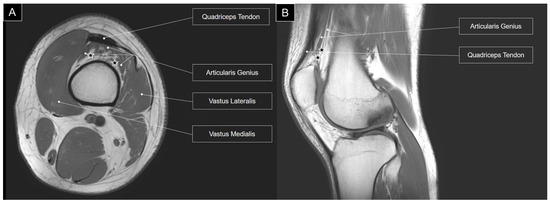

Additionally, a more substantial presence of fatty tissue was identified in the deeper portion of the articularis genus muscle [7]. This fatty infiltration is further highlighted in T1-weighted magnetic resonance imaging, where high-intensity fat tissues are discernible within the articularis genus muscle (Figure 4).

Figure 4. T1-weighted axial (A) and sagittal (B) views of magnetic resonance imaging for the articularis genus muscle. Stars, fat tissue.